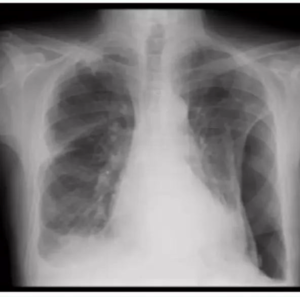

• Miliary TB refers to widespread dissemination of TB by hematogenous spread.

• Seen more frequently in reactivation TB.

The characteristic radiographic and high-resolution CT findings consist of innumerable, 1- to 3-mm diameter nodules randomly distributed throughout both lungs